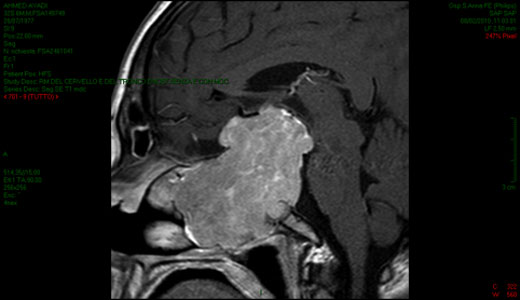

Nell’ambito della patologia ipofisaria si presentano le immagini di un adenoma ipofisario gigante che ha reso necessario un intervento con approccio combinato trans-facciale.